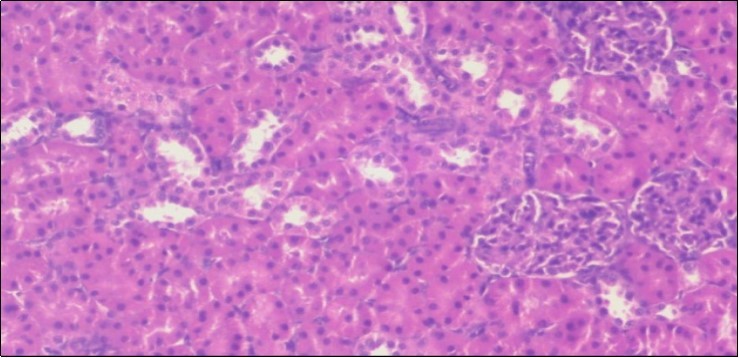

The histological examination of the kidney of the control rats fed on a standard diet showing normal rounded capsules with normal Bowman's glomeruli, round proximal tubules and elongated distal tubules with high cuboidal cells figure 1. The rats fed (HFD) showed fatty degeneration of the tubules with eosinophilic material deposition, glomerular atrophy with wide urinary space and distal tubules with extrusion of nuclei into lumen figure 2. By comparison kidneys of rats which were treated by fennel after being obese and the control rats observed partial improvement in both Bowman's capsules and proximal tubules. Note the distal tubules show less focal fatty infiltration figure 3.While examination of rats kidney that were treated by ator after obesity showed improvement in Bowman's capsules with normal glomerular and partial improvement in proximal tubules and distal tubules, figure 4. Kidney of rats that were treated by fennel and ator after obesity and the control rats showed high improvement in the tissues with normal glomerular and that Most of Bowman's capsules and renal tubules, restoring their normal appearance figure 5.

Figure 3.Photomicrogragh of kidney section of treated rat with fennel herb showing partial improvement in both Bowman's capsules and proximal tubules. Note the distal tubules show less focal fatty infiltration, (H&E) (40X)

Figure 4.Photomicrogragh of kidney section of treated rat with Ator drug showing improvement in Bowman's capsules with normal glomerular and partial improvement in proximal tubules and distal tubules, (H&E) (40X).